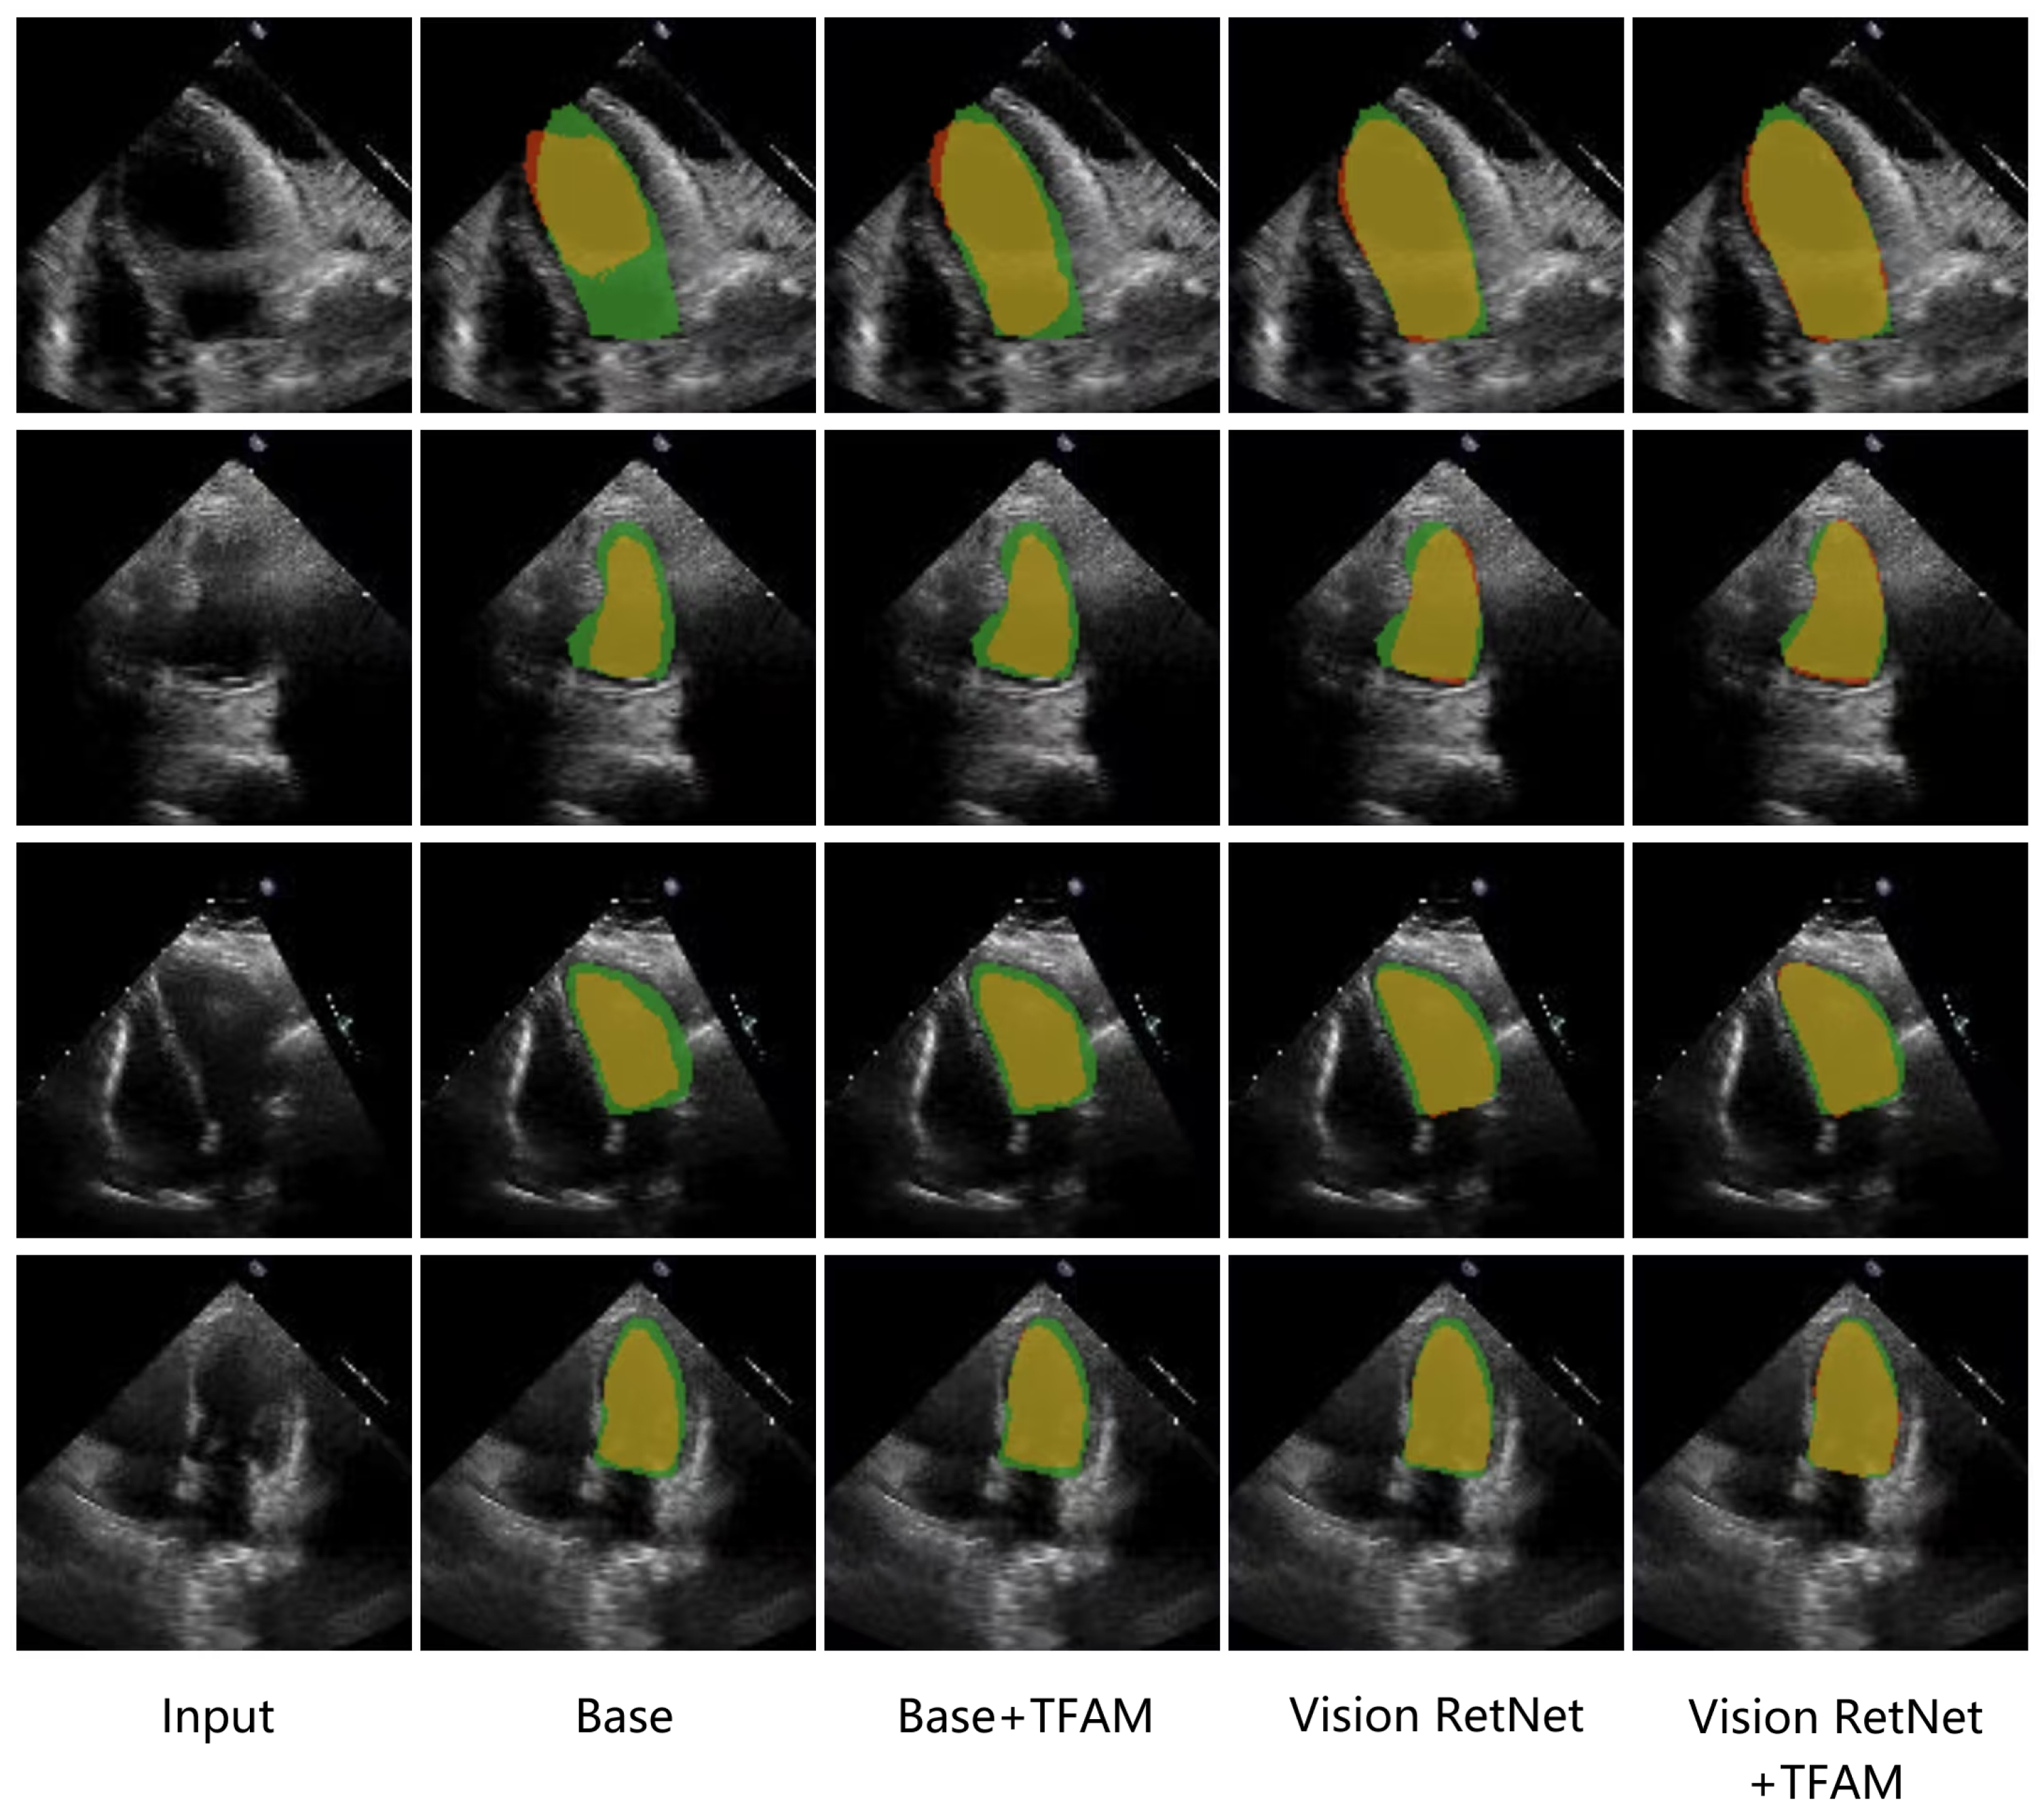

4.4.2. Ablation Study

| Setting | DSC (%) ↑ | HD95 (Pixels) ↓ |

|---|---|---|

| Baseline(UNETR) | 92.43 | 3.06 |

| Baseline+TFFM | 92.49 | 3.04 |

| Baseline+Vision RetNet | 92.95 | 2.72 |

| Vision RetNet+TFFM | 93.17 | 2.72 |